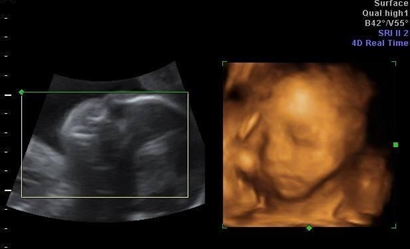

四维彩超是实时的立体成像,在孕检的时候主要是帮助筛查胎儿的畸形,四维由于清晰度高也有用来判断胎儿男女,那么四维看是男孩有可能是女孩吗,四维男翻女的几率多大?

四维彩超其实是实时的三维,是有一个立体成像的过程,因为胎儿是团抱式的,胎儿一部分会被遮挡,所以四维应该会更准确一些,但是不是绝对的。实际在B超进行胎儿性别鉴定时,有可能男孩生殖器被遮挡导致误认为是女孩,也可能把女孩的脐带当成生殖器误认为男孩,当医生正在操作B超的时分,若宝宝正处于背部的姿态或手脚正好蜷到一同,从而遮挡了性别器官,这也会形成性别的改动,另外假如你***宝太调皮了,不太配合,姿态不对,医生也不可以很精确的看到Ta的生殖器,结果就没有那么精确了,因此四维彩超虽然是比较精确的,但是也会出现错误的情况。

四:通过四维彩超图看清胎儿性别,在六个月以后照四维彩超,只要宝宝的姿势是正面不是给个背影什么的,是男是女一看就知道。不过因为国家明文规定不能查胎儿性别,所以医生不会把能明显看出性别的一面照给妈妈看。